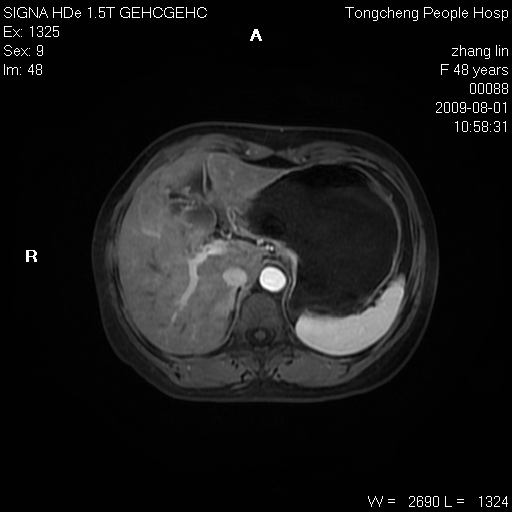

女,48岁。健康体检,彩超发现右肾占位性病变。平素健康。

临床诊断:右肾占位性病变,性质待定(囊肿?肿瘤?)。

上中腹部mr平扫+增强扫描,图像如下:

右肾上极见一类圆形病灶,t1wi呈等信号t2wi呈等高混杂信号,三期增强无强化,边界清---考虑囊肿出血。

同反相位均表现为等信号,病变无强化,考虑含蛋白的囊肿可能,弥散加权相或许有些帮助,

肝囊肿

慢性胆囊炎